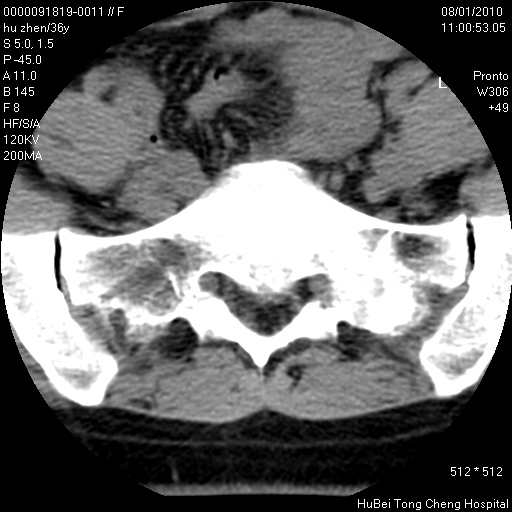

患者 女,36岁。右侧腰腿痛半月余。腰骶椎mr平扫偶然发现骶椎异常信号。

临床诊断:1)腰椎间盘突出症。2)骶椎肿瘤性病变?

骶椎ct平扫(层厚、层距均为5mm),图像如下: